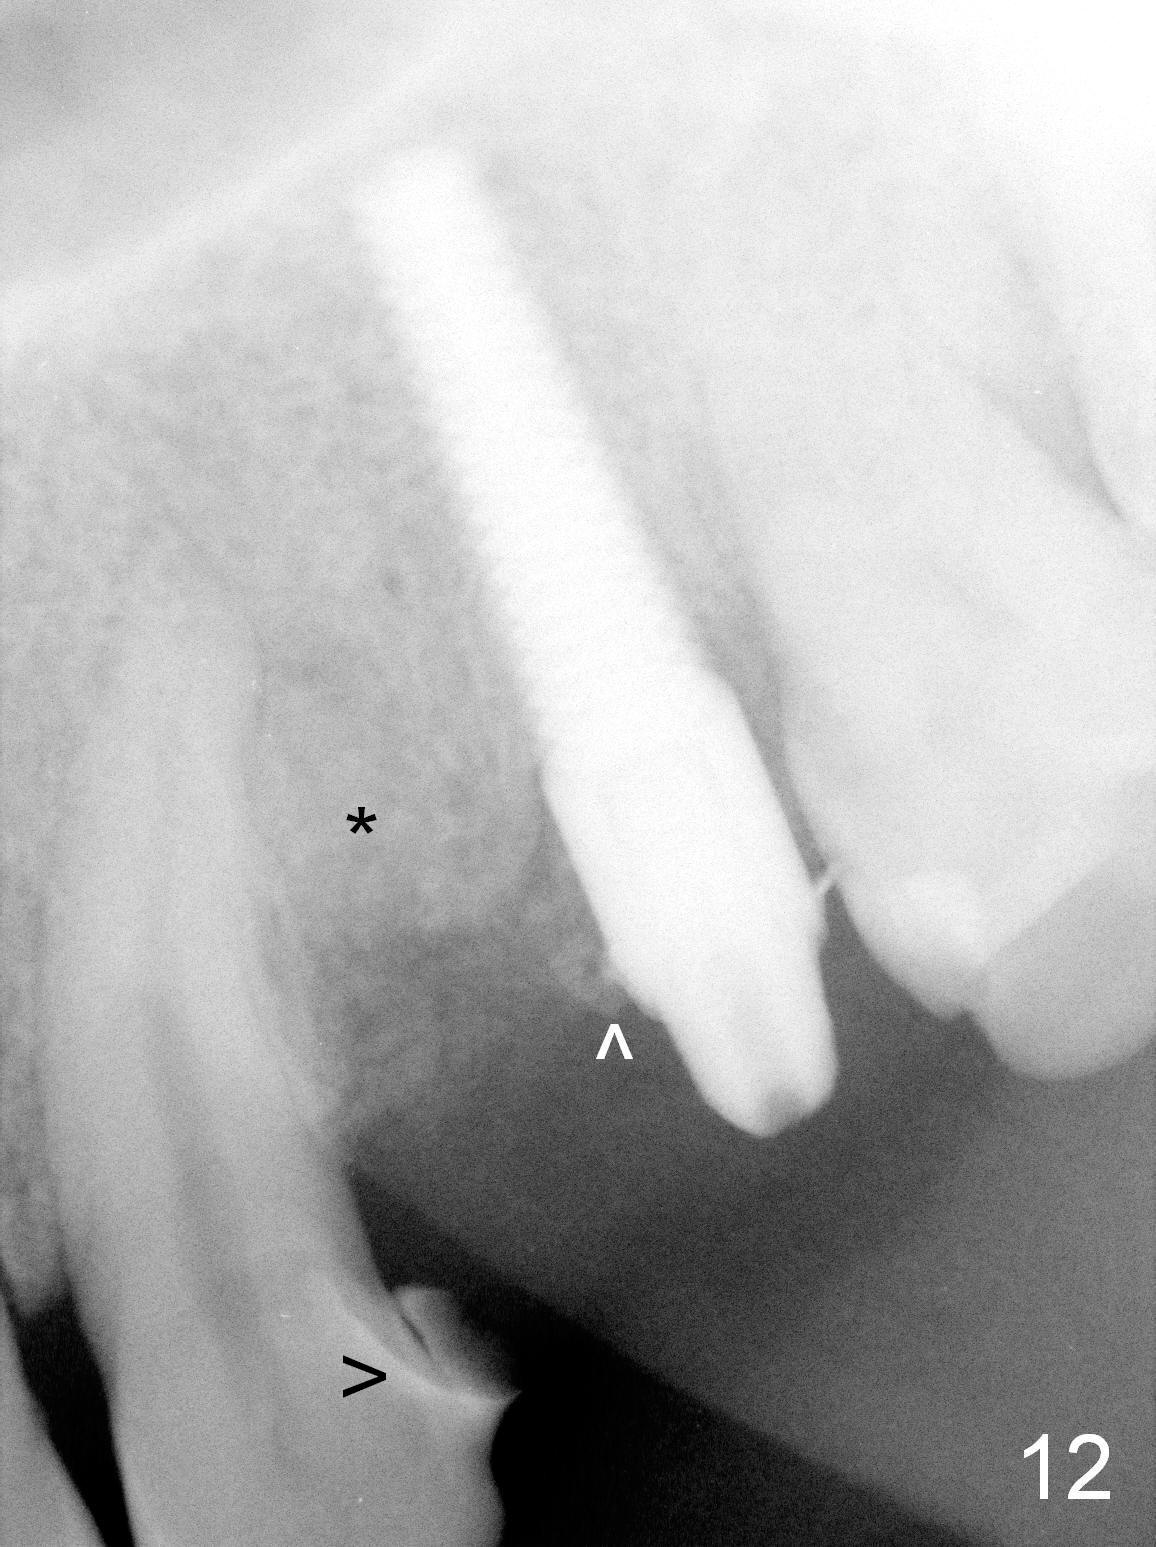

Taking 2 additional PAs with sensor 1 is frustrating (Fig.1,2), no apices shown. Osteotomy is done smoothly with 2 mm pilot drill at 20 mm, 2.5 mm reamer at 17 mm, and 3 mm reamer at 14 mm and 4.5x20 mm tap at 17 mm. The 1st intraop PA is taken with sensor 1 when 2 of 4.5x20 mm implants are placed (Fig.3); the implant at #12 is close to the root of the tooth #11. The 2nd PA is taken with sensor 2: the apex of #11 touches the implant at #12 (Fig.4). There is no separation when panoramic X-ray is taken (Fig.5). Effort is exerted to re-direct the osteotomy twice (Fig.6: tap; Fig.7: implant) without success. When the implant is removed, a PA is taken; it appears that the root of the tooth #11 has no damage (Fig.8). To obtain the best recovery, socket preservation is carried out with 50/50 cortical/cancellous allograft mixed with Osteogen (Fig.12 *) and Collagen Dressing (Fig.9: #12). A 2 (or 3)-unit provisional bridge (Fig.10: #12,13) is fabricated over the implant (Fig.9 I)/abutment (A) to cover these 2 sockets. After acid etching #11 D surface (Fig.9 >) and relining (Fig.11 *), the provisional bridge is bonded to the tooth #11 (Fig.11,12 black >) so that bone graft will be less likely dislodged.